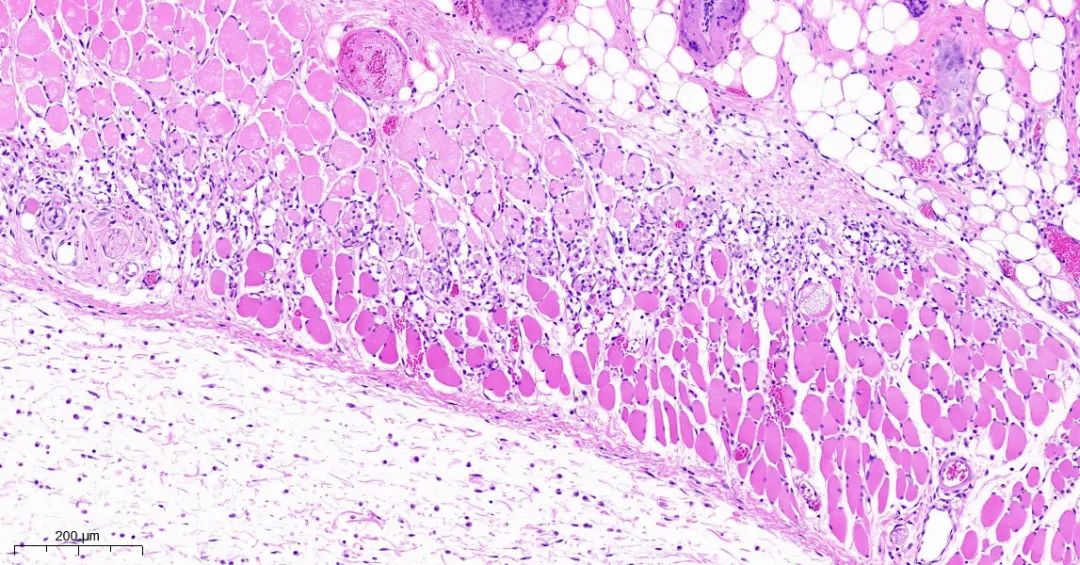

取正常对照组及模型组大鼠背部皮肤标本,常规固定,石蜡切片,HE染色,观察皮肤组织学变化。

模型1组皮组织切片对比

模型2组皮组织切片对比